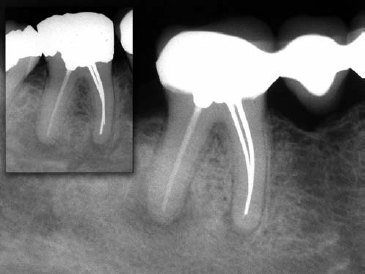

Fig 1. Examples of procedural errors during treatment that lead to failure. (A) Case 1, poor access cavity design, open access cavity and breakdown of the amalgam restoration. (B) Case 2, missed canal and poorly instrumented and obturated canals.

It is generally acknowledged that persistence of disease is most commonly due to difficulties that occur during initial endodontic treatment. Inadequate aseptic control, poor access cavity design, missed canals, inadequate instrumentation, and breakdown of temporary or permanent restorations are examples of procedural pitfalls that may result in persistence of endodontic disease (Fig 1).42